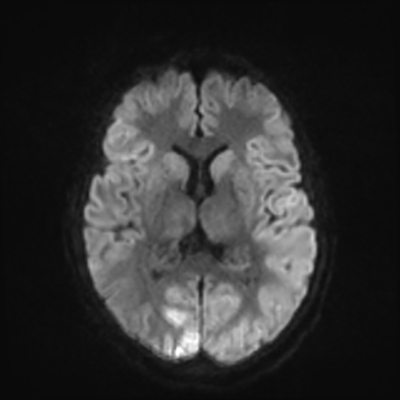

MRI brain (DWI)

MRI brain (DWI) 4/24 4/24

You can clearly see diffuse cortical and basal ganglia diffusion restriction, and that of his deep cerebellar nuclei as well. The right occipital lobe abnormalities are a little more prominent, but then you remember that he is known to have had a right occipital stroke weeks ago.

In reviewing his data, you know that he doesn't have any of the strong predictors of a poor neurologic prognosis. However, based on these findings on MRI, along with the absent reactivity on cEEG, you are able to tell the primary team and the patient's family that he is likely to have a poor prognosis, based on these multiple moderate predictors. Recovery is not completely impossible-- there is more uncertainty with this prognostication than if we were able to get SSEPs-- but you're very worried about his outlook and that any potential recovery would require a very protracted rehabilitation period. Given his high cervical cord injury level, tracheostomy would be required anyway. So, it comes down to whether his family thinks he'd want to pursue these aggressive measures.